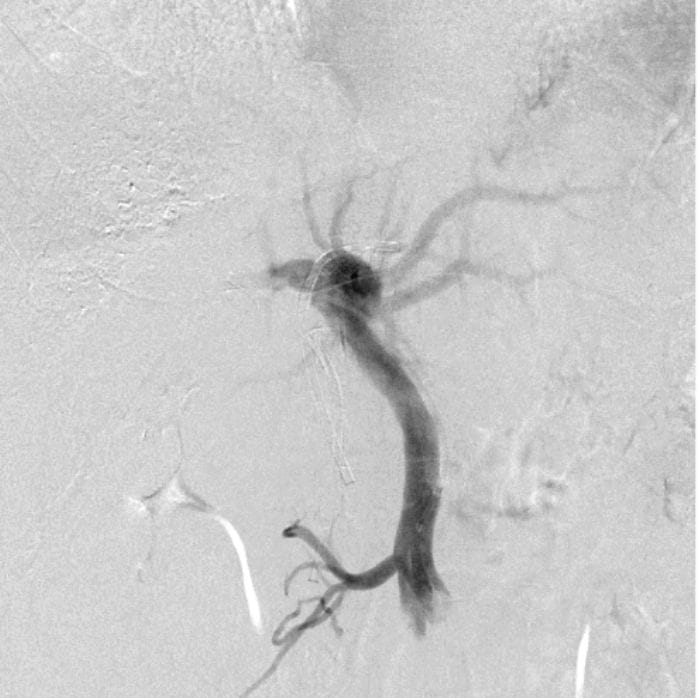

大型動脈瘤や血管そのものが動脈瘤化した紡錘状動脈瘤に対して、これまでの治療法では理想的な根治的治療が困難でありました。これらの治療困難な動脈瘤を対象とする脳血管内治療機器としてFlow Diverter と称されるステントが開発され臨床使用が始まりました。Flow Diverterステントは従来の血管内治療と異なり、脳動脈瘤内にカテーテルを誘導しコイルなどの塞栓物質を充填することなく、動脈瘤に流入する血行を制御することにより、動脈瘤の破裂や増大を防ぎつつ、親動脈を温存するという画期的なものであります。使用施設が限定されている治療方法ですが、東京医科大学病院では2020年よりこの治療を行っております。